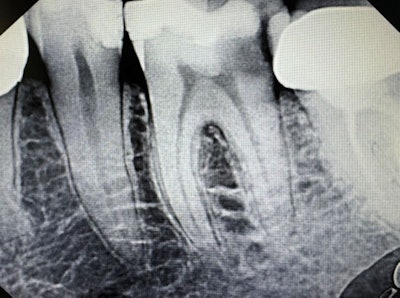

Symptomatic irreversible pulpitis with symptomatic periapical periodontitis.Dr. Deepika Ganne.

Complete pulp tissue removal and total debridement of the root canal are recommended with occlusal bite reduction. If root canal therapy cannot be completed due to time constraints, then placement of intracanal medicaments such as calcium hydroxide helps reduce the chances of bacterial growth in between appointments.

Anti-inflammatory medications are recommended. No antibiotics need to be prescribed.